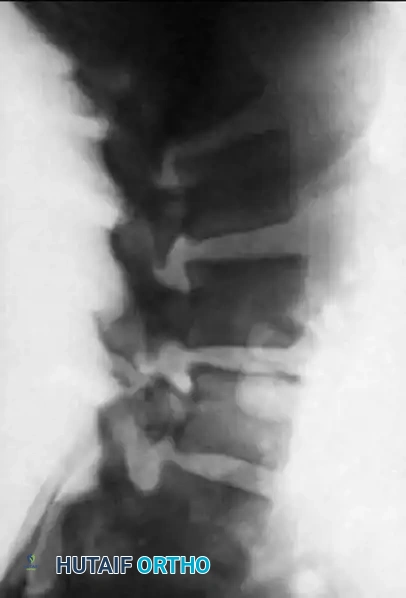

* Standing AP and Lateral Views: Essential for evaluating the true extent of the deformity. Up to 15% of deformities spontaneously reduce when the patient is supine.

Preoperative standing lateral radiograph demonstrating a Grade I degenerative anterolisthesis of L4 on L5 with associated disc space collapse.

- Flexion-Extension Lateral Views: Utilized to assess dynamic instability. Instability is generally defined as >4 to 5 mm of dynamic translation or >10 to 15 degrees of angular change between flexion and extension.